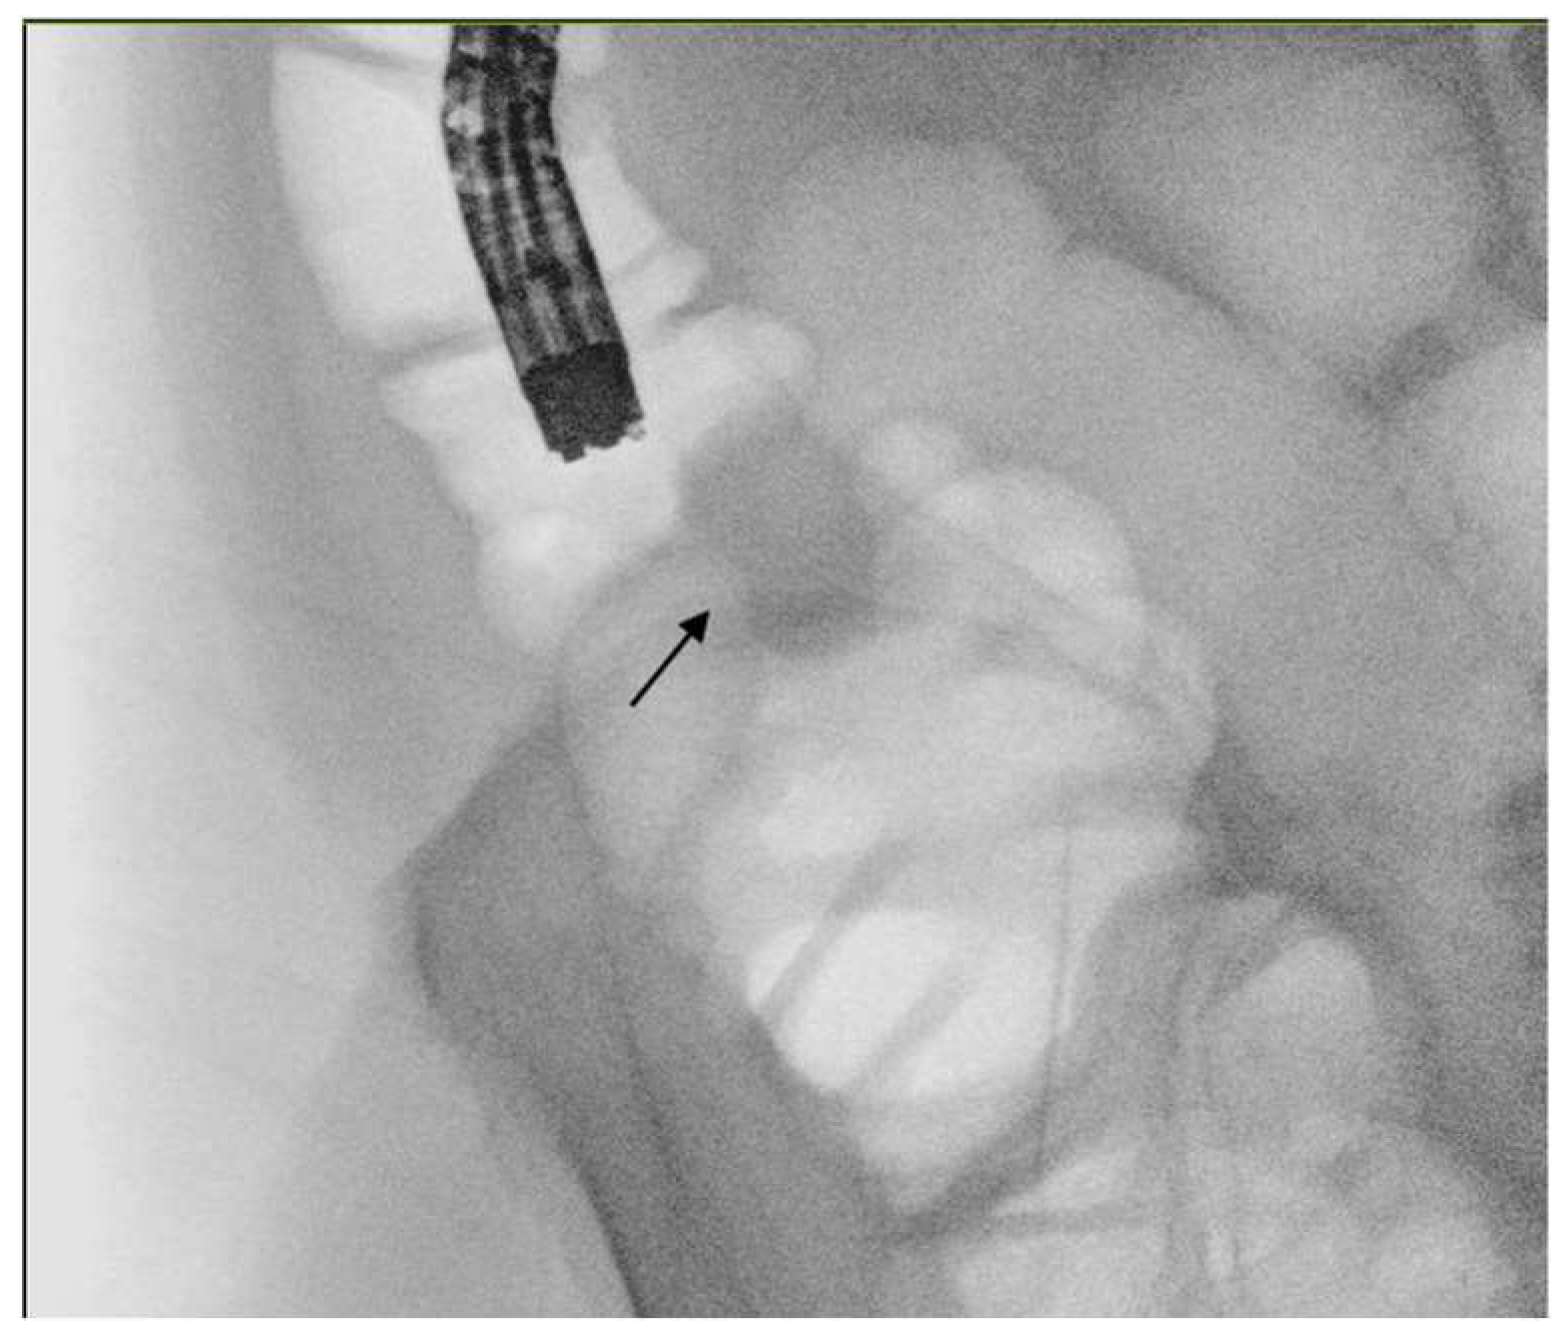

5.2. Technique